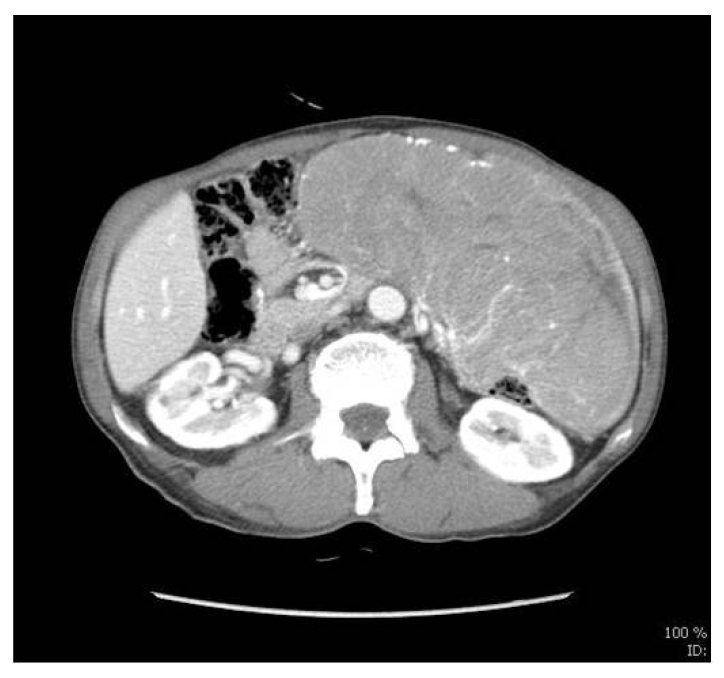

방사선 소견: 입원 후 시행한 흉부 단순 촬영은 정상이었고 복부 전산화단층촬영(Fig. 1)에서 좌측 상복부 그물막에서 조영 증강되는 거대한 종괴가 확인되며 주변으로 풍부한 혈관분포가 관찰되었다. 주변으로 장폐쇄, 림프절의 비대 및 전이소견은 보이지 않았으나 소량의 복수가 확인되었다. 전신 양전자방출단층촬영 검사에서 복부 전산화 단층 촬영에서 보였던 종괴와 같은 위치로 F-18 fluorodeoxyglucose 섭취가 증가된 거대 종괴가 관찰되었다.

Figure 1.

Bulky delayed-enhancing mass in the omentum of the left upper to mid abdomen, with a high supply of blood from the surrounding dilated mesenteric omental arteries.